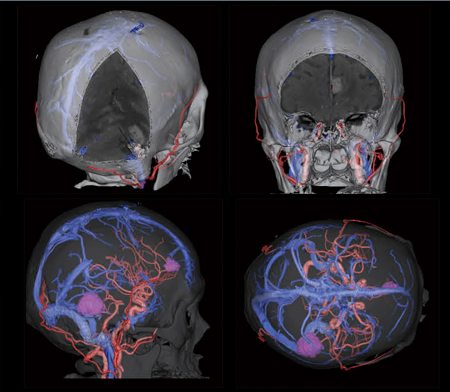

Neuro部門

高田忠徳

(金沢大学附属病院放射線部)

【背 景】71歳,男性。転移性脳腫瘍疑いで外科的手術目的に入院。手術用ナビゲーションシステムを用いたImage-Guided Surgeryを予定しており,静脈と動脈の走行を把握できるよう頭部全体のCTA/CTV,血管・腫瘍・骨との位置関係を把握するために正確な三次元画像の作成を依頼された。

【所 見】肺腺癌の多発脳転移疑い。右側頭葉への転移は27mm大で周囲への浮腫が強く,側脳室圧排およびmidline shiftを認める。左前頭葉への転移は22mm大で,左大脳鎌への髄膜転移と考えられる。こちらは前大脳動脈が腫瘍内を走行している。

【ポイント】当院における従来のプロトコルは,(1)頭部単純CT(コンベンショナル),(2)Dual Energy(頭蓋骨除去目的)でのCTA/CTV,(3)腫瘍確認の頭部造影CT(コンベンショナル)であった。このプロトコルではCTVでの腫瘍造影効果が低く,三次元画像作成時に正確な腫瘍範囲を抽出することが困難であった。また,撮影回数が多いため,被ばくの面でも問題であった。そこで,今回の症例ではこれらの問題点を解決するために,次のような工夫を取り入れた。(1)撮影手順の改善:CTA撮影(造影剤は50mLのみ投与)→90秒のdelay time(腫瘍が濃染)→CTV撮影(残りの造影剤50mL投与)。これにより,CTVで腫瘍が十分に濃染しているため,三次元画像の作成が容易になった。また,CTVの画像から5mm厚の画像を再構成することで,従来の頭部造影CT(コンベンショナル)を省略でき,検査トータルでの被ばく線量を低減できた。

(2)Dual Energyの併用により,骨と静脈の正確な分離が可能となった。(3)CTA/CTVにSAFIRE(Strength3)を使用することで,従来のプロトコルより10%の線量低減が可能となり,さらに,骨と静脈の分離精度が向上した。